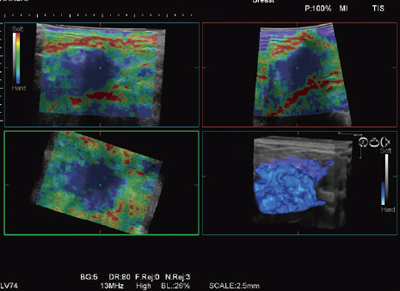

“Real-time Tissue Elastography”は組織の硬さの違いを画像化する技術で,2003年に日立が世界で初めて製品化しました。現在では,乳がん検診をはじめとした日常検査でも使用されるようになってきています。HI VISION Ascendusには,世界で初めてリアルタイムでElastographyを3D表示する機能を搭載しました(図3)。この機能は,リニア探触子を機械的に揺動させることでボリュームデータをリアルタイムに取得し,組織の硬さ情報を画像化します。この機能の実現には,高速の信号処理能力が要求されますが,Ultra BEUにより初めて実用化しました。

図3 4D Elasto